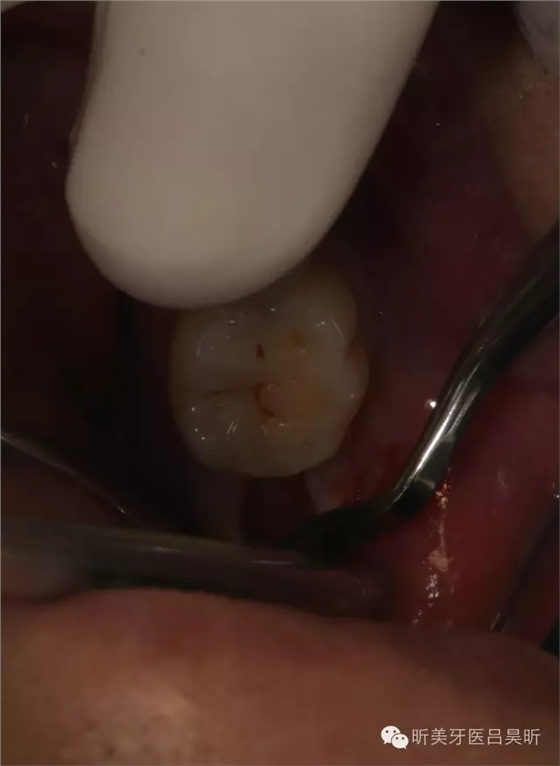

術(shù)前口內(nèi)檢查,可見牙槽骨寬度良好,角化齦量適中

術(shù)前口內(nèi)掃描,設(shè)計冠修復(fù)方式和種植位點(diǎn)

可見種植位點(diǎn)舌側(cè)區(qū)凹陷,牙槽骨上部舌傾明顯。